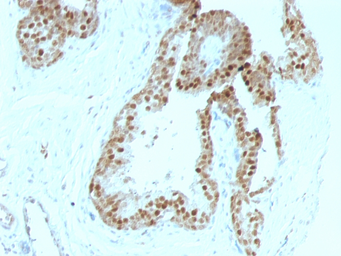

GTX34941 IHC-P Image

IHC-P analysis of human colon carcinoma tissue using GTX34941 p57 Kip2 antibody [KIP2/880].